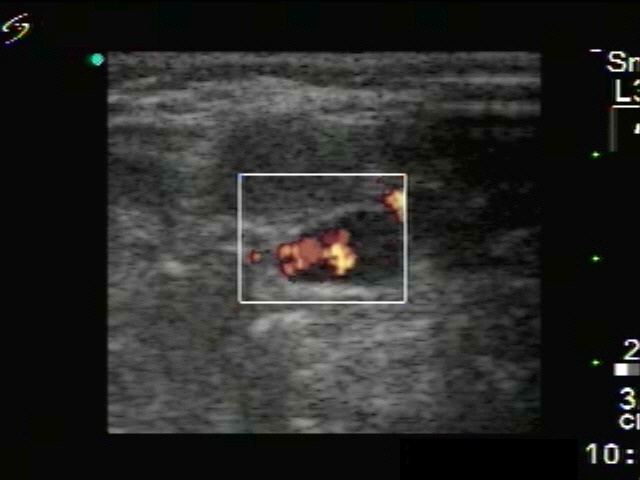

Intranodular hyperechogenic figures - case 1774 (ultrasonographic picture 5)

Left side of the neck, above the left lobe, transverse view, power Doppler mode. No vascularization can be detected within the lymph node.